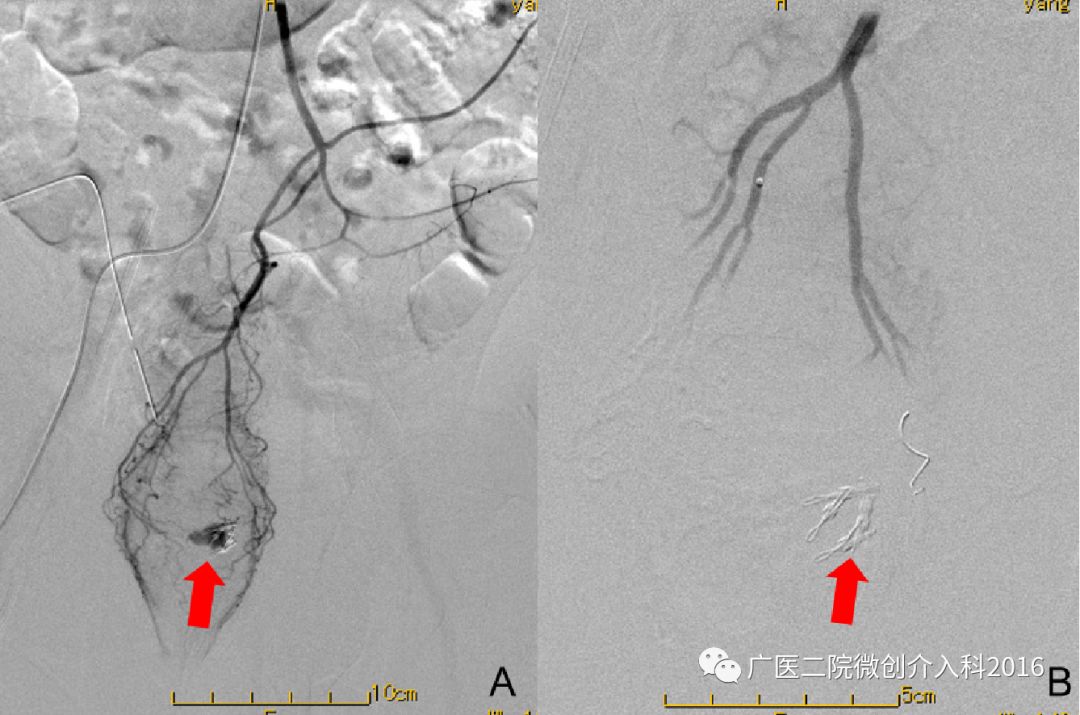

病例1:肝硬化导致的食管胃底静脉曲张破裂出血

患者为肝硬化导致的食管胃底静脉曲张破裂出血,图A可见胃底粗大的曲张静脉。我们通过经颈静脉肝内门体分流术(TIPS)联合曲张静脉栓塞术(PTVE),一方面通过TIPS分流降低门静脉压力,另一方面通过PTVE栓塞出血的曲张静脉,共同达到减压、止血的目的。图B可见TIPS分流术后门静脉至肝静脉的分流通道,PTVE栓塞术后原曲张静脉消失。术后患者出血立即停止,生命体征逐渐平稳,止血效果立竿见影。